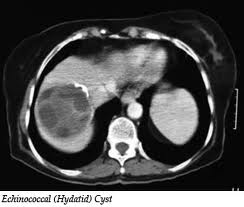

Second reported case of multilocularis hydatid disease in Iraq

A.K. Zeki Benyan, N. K. Mahdi, F. Abdul-Amir, O. Ubaid

365-366